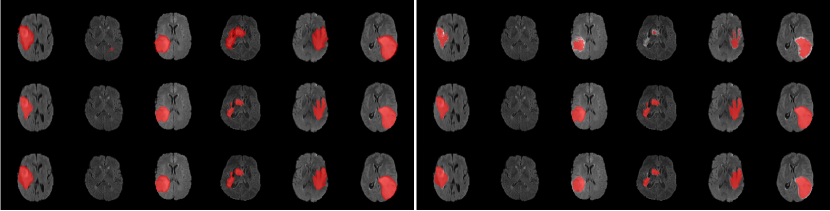

Synthetic noise settings. We use three public medical image datasets, JSRT dataset (Shiraishi et al., 2000), ISIC 2017 dataset (Codella et al., 2017), and Brats 2020 dataset (Menze et al., 2015; Bakas et al., 2017b; 2018; a). JSRT contains 247 images for chest CT and three types of organ structures: lung, heart and clavicle, all with clean ground-truth labels (Juhász et al., 2010). We randomly split the data into training (148 images), validation (24 images), and test (75 images) subsets. ISIC 2017 is a skin lesion segmentation dataset with 2000 training, 150 validation, 600 test images. Following standard practice Zhu et al. (2019); Zhang et al. (2020b); Li et al. (2021), we resize all images in both datasets to in resolution. Brats 2020 is a brain tumor 3D segmentation dataset with 369 training volumes. Since only training labels are accessible, we randomly split these 369 volumes into training (200 volumes), validation (19 volumes) and test (150 volumes) subsets. We resize all volumes to in resolution.

For each of these three datasets, we use three noise settings, denoted by , and . and are two settings synthesized by our Markov process with (expansion) and (shrinkage), respectively. Figure 4 shows examples of our synthesized label noise. We also include the mix of random dilation and erosion noise used by previous work (Zhu et al., 2019; Zhang et al., 2020b; a). This is achieved by randomly dilate or erode a mask with a number of pixels. Note that our Markov label noise can theoretically include this type of noise by setting . Detailed parameters for these settings are provided in the Appendix.

Table 1 shows the segmentation results of different methods with synthetic noisy label settings on JSRT , ISIC 2017 and Brats 2020 dataset. Note that QAM cannot be applied to Brats 2020 dataset because their network is designed for 2D only. We compare DICE score (DSC) on testing sets (against the clean labels). For each setting, we train 5 different models, and report the mean DSC and standard deviation. In and , where biases show up in noisy labels, the proposed method outperforms the baselines by a big leap in total case. The compared methods, however, only work when little bias is included, like . is equivalent to setting in our Markov model, resulting in . We also test the proposed method on real-world label noise, results shows in Table 2. Figure 5 shows examples of label correction results. We provide more qualitative results in the Appendix A.4.